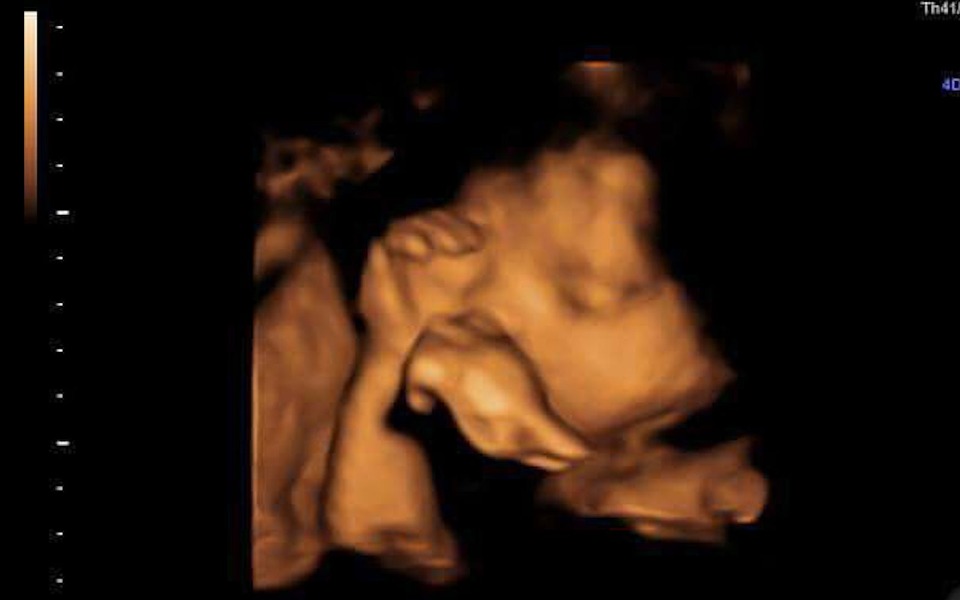

Dzień dobry państwu jestem 17letnią mamą.

Zbieram pieniążki na akcesoria dla mojej nie narodzonej córci zostało nam jeszcze 2 miesiące 😃❤ Pieniążki zostaną wykorzystane w celu kupienia pampersów, pieluszek butelek i najpotrzebniejszych akcesorii, bardzo mi przykro o tym mówić ale zostałam tak naprawdę w tym wszystkim sama 😔 Będę ogromnie wdzięczna chociaż za symboliczną złotówkę!❤